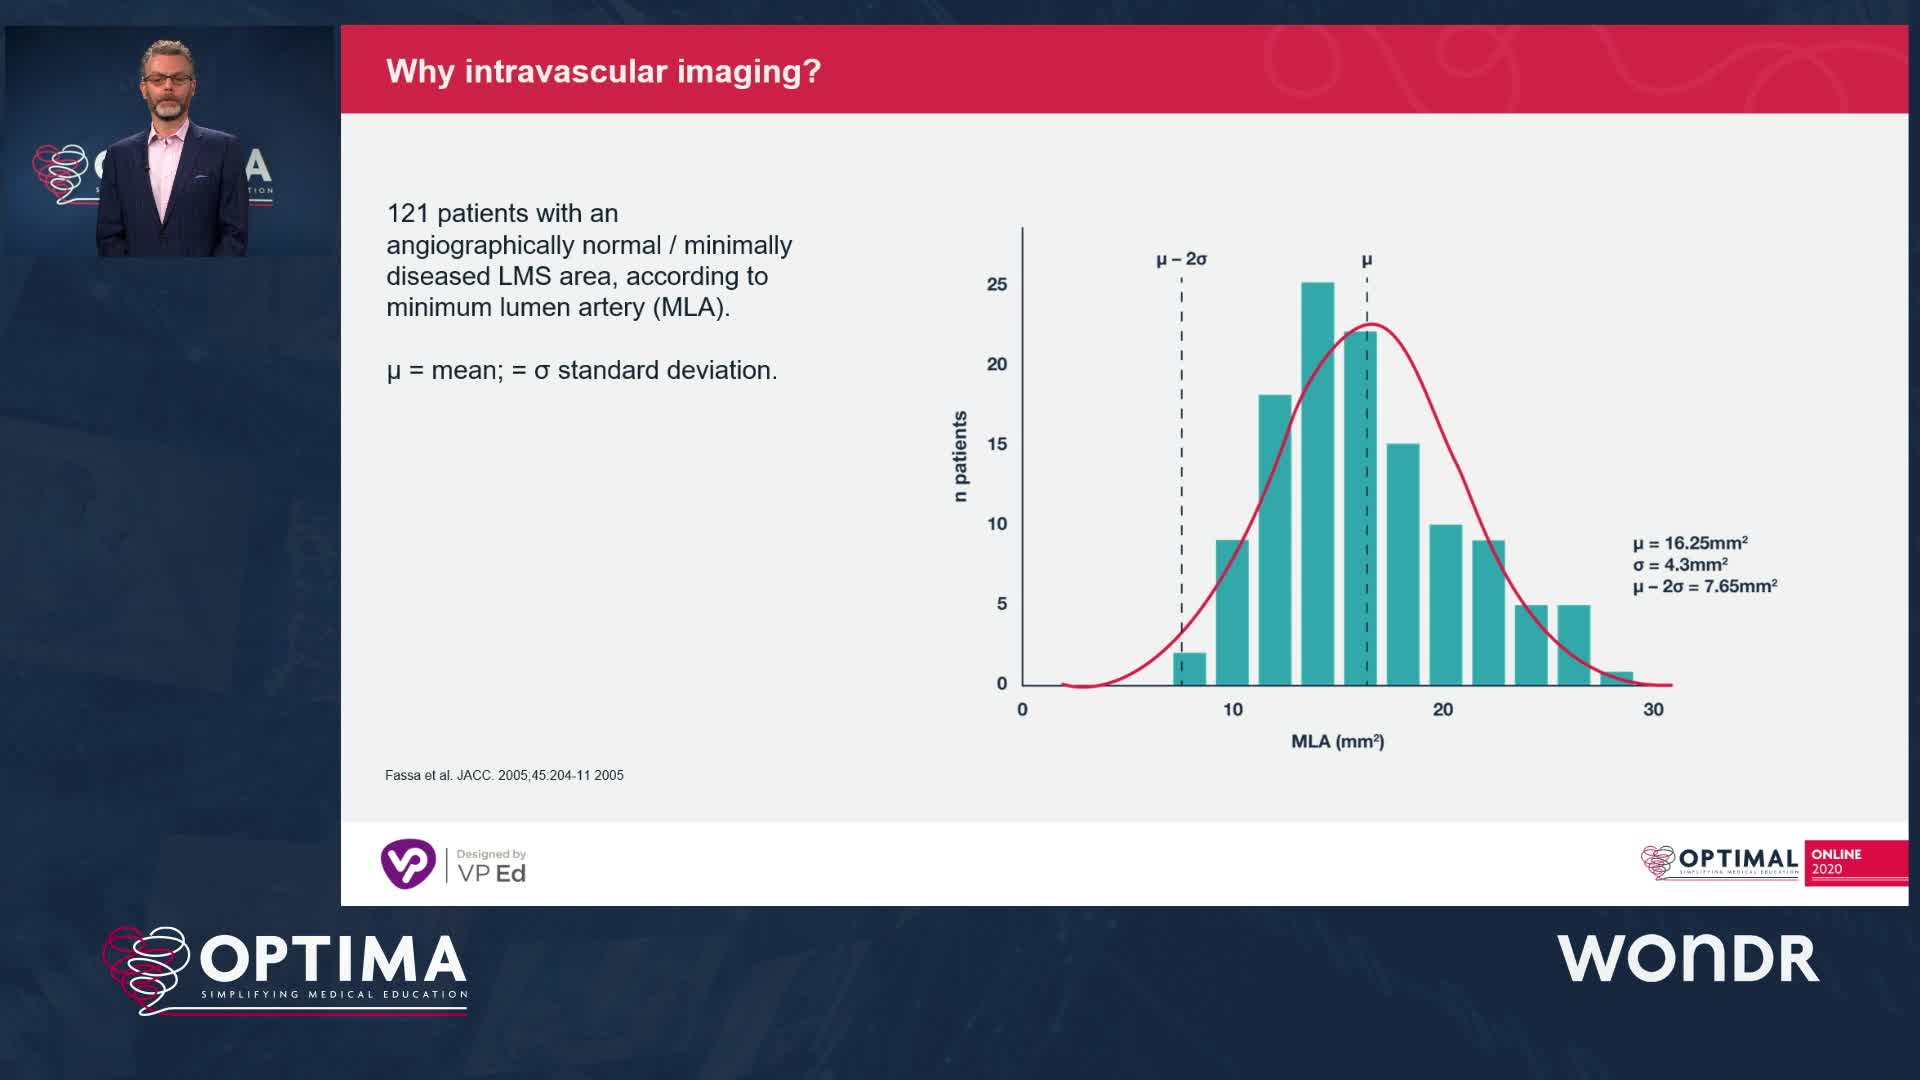

The integrated use of physiology and imaging is transforming the treatment of complex bifurcation disease. We explore...